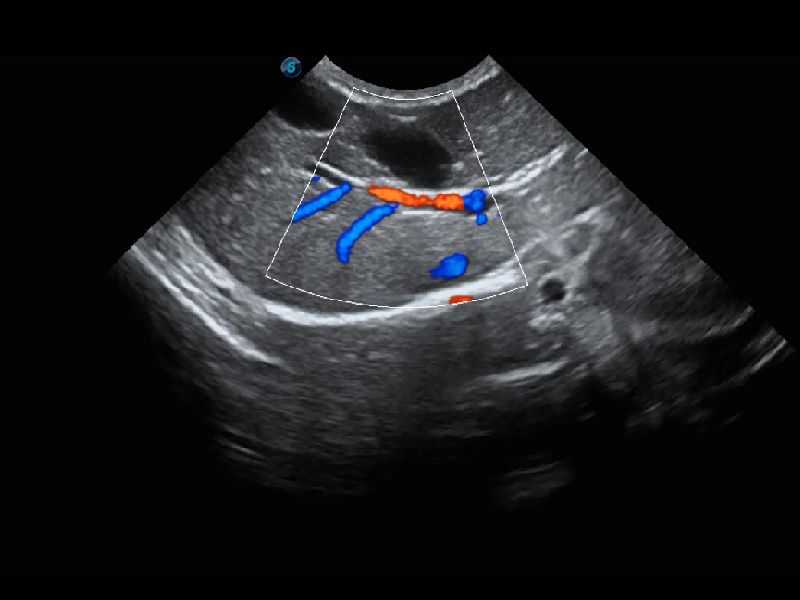

(猫)髂动脉血流频谱